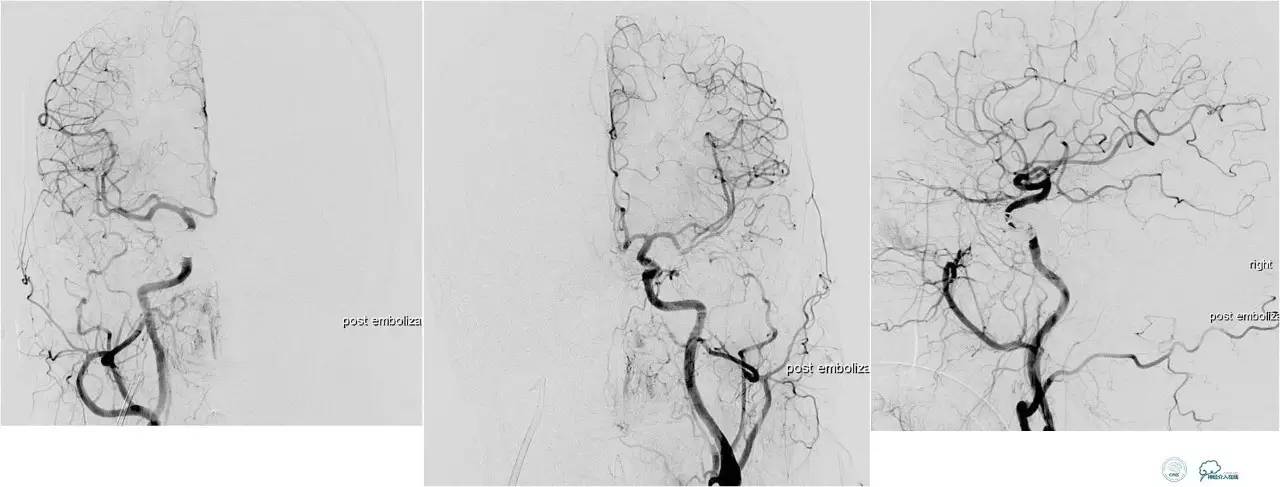

脑膜后动脉供血的小脑幕的瘘。

颈内不参与供血。

大脑后动脉有细小分支供血。

Sceptor球囊无法到达瘘口位置,放在主干内,充盈球囊后把动脉血管床内血液冲洗干净,形成楔入效果。

术后造影【Post embolization】